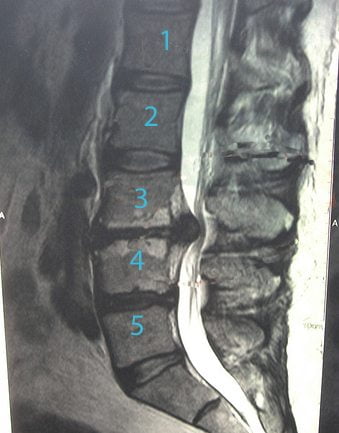

Во время процедуры врач контролирует свои действия с помощью специального оборудования. Но необходимо и предварительное обследование пациента. Наиболее информативна магнитно-резонансная томография. На полученных изображениях отчетливо визуализируется грыжевое выпячивание, его форма, размеры. Немаловажен и вид смещения межпозвонковых дисков — дорзальный, латеральный, фораминальный, боковой. С помощью МРТ можно оценить состояние кровеносных сосудов, мышц, спинномозговых корешков, чтобы правильно рассчитать дозы препаратов, а при необходимости — дополнить терапевтическую схему.